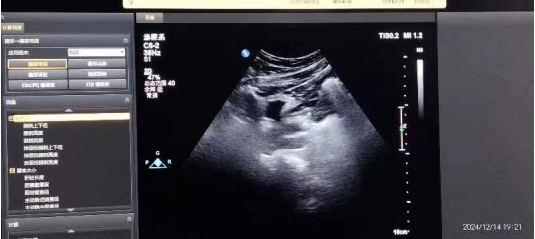

體外沖擊波碎石,利用超聲定位,將沖擊波精準(zhǔn)作用到腎或輸尿管結(jié)石處,在不停地“擊打”下,結(jié)石便會(huì)層層剝離,最終變?yōu)榉勰F鋬?yōu)點(diǎn)包括創(chuàng)傷小、恢復(fù)快、操作方便、無需麻醉、費(fèi)用低,對(duì)于結(jié)石較小且無其他嚴(yán)重全身疾患的患者,在門診就可進(jìn)行治療。